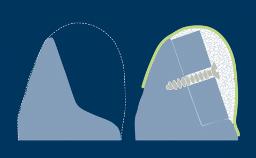

O uso de próteses dentárias implantossuportadas para substituir dentes perdidos resultou em um foco renovado nas técnicas de extração, particularmente na zona estética. A remoção do dente sem danificar o alvéolo pode facilitar a cicatrização pós-operatória, as técnicas de preservação do rebordo e a subsequente instalação do implante. Este módulo descreverá as técnicas para remover um dente condenado, com a instalação do implante em mente.

- selecione a técnica de extração minimamente traumática mais apropriada para remover um dente